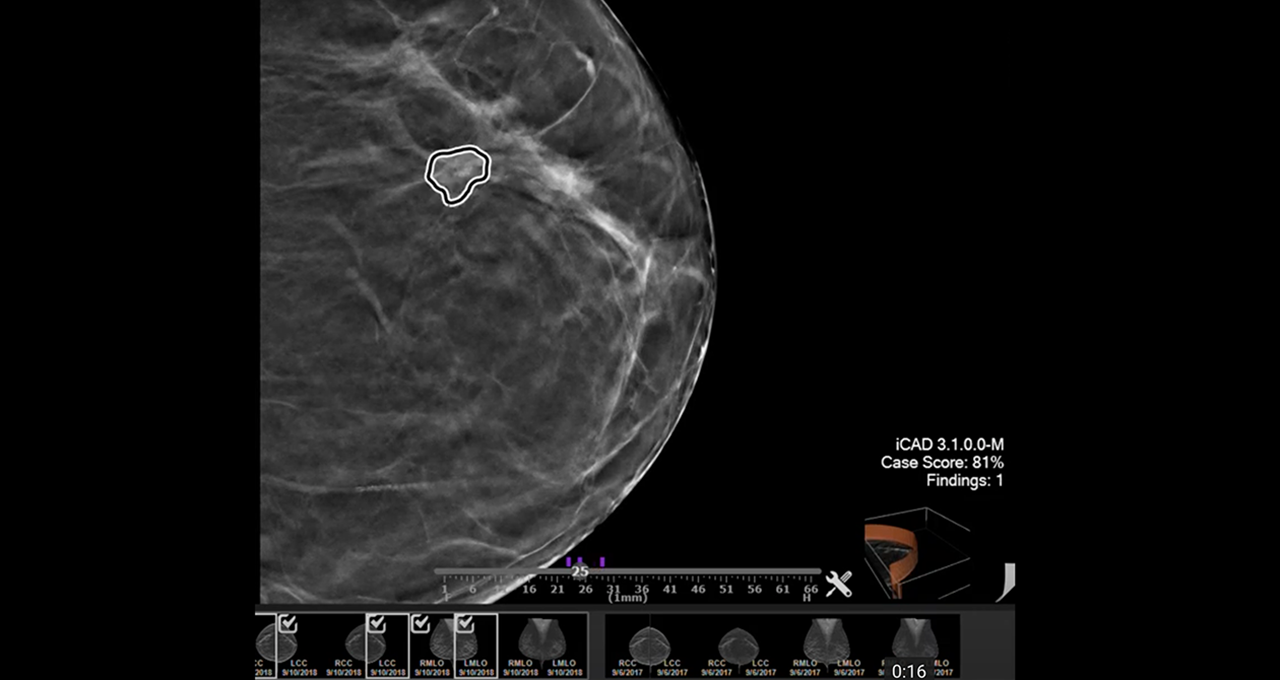

图注:NVIDIA AI Enterprise使医院的IT管理员能够在医院的核心应用程序旁上运行AI应用程序,例如用于乳腺检查的iCAD Profound AI软件。

NVIDIA AI Enterprise为在虚拟化基础设施上托管各种医疗健康和运营应用程序的组织简化了AI部署体验。它使IT管理员能够将Vyasa和iCAD等AI应用程序与医院的核心应用程序结合运行,从而在他们熟悉的环境中简化工作流程。

放射科医生使用iCAD的创新ProFound AI软件协助解读乳房X光片。这些AI解决方案能够帮助更早地发现癌症、对乳房密度进行分类,并根据每位女性的乳房X光筛查结果,准确评估个人短期内的乳腺癌风险。使用VMware vSphere运行高级工作负载对于iCAD的医疗健康客户至关重要,因为他们可以轻松地将其数据密集型应用程序集成到任何医院的基础设施中。